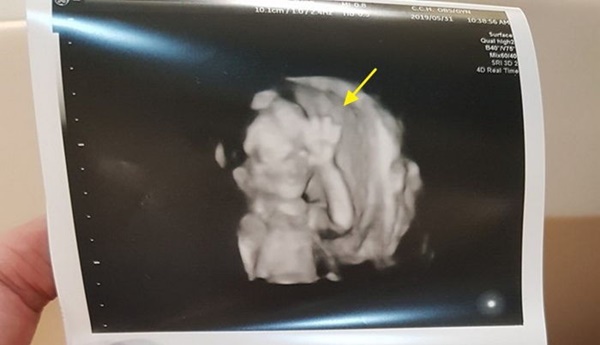

Vào ngày 31/5 vừa qua, một ông bố ở Đài Loan đăng lên Facebook ảnh chụp siêu âm của con với dòng caption: "Con tôi chào mọi người đây, tôi tò mò không biết những đứa trẻ khác có như vậy không?" và thu hút sự chú ý của đông đảo dân mạng. Theo đó, đứa trẻ này dường như biết được bác sĩ đang chụp hình siêu âm 3D nên đã giơ tay vẫy chào, miệng có vẻ cũng mỉm cười. Sau đó, đứa trẻ tinh nghịch này còn chuyển sang giơ tay chữ V. Bác sĩ cũng cho biết đây là lần đầu tiên họ nhìn thấy đứa trẻ hành xử như vậy trong lúc chụp hình siêu âm.